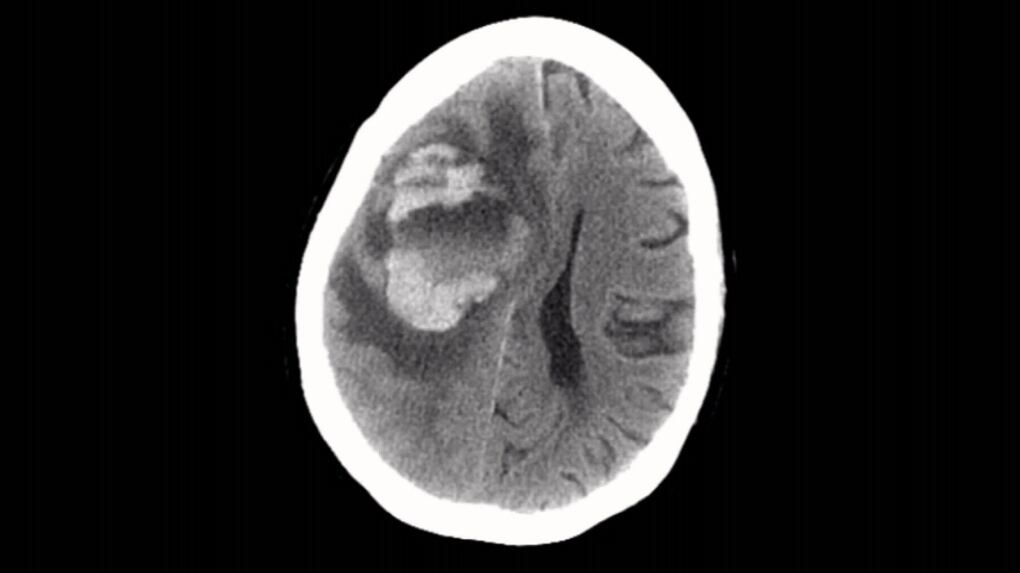

Doctors blame tap water in neti pot for brain-eating amoeba